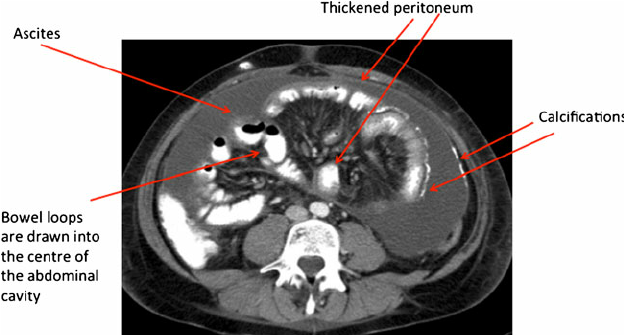

• 피낭성 복막 경화증 (Encapsulating Peritoneal Sclerosis, EPS)

• 장기간 복막 투석의 심각한 합병증

• 복막이 두꺼워지고 장 유착 발생 → 장폐색, 영양실조

• 치료: 투석 중단(HD 전환), 수술(박리술), Tamoxifen, Steroid 등 시도